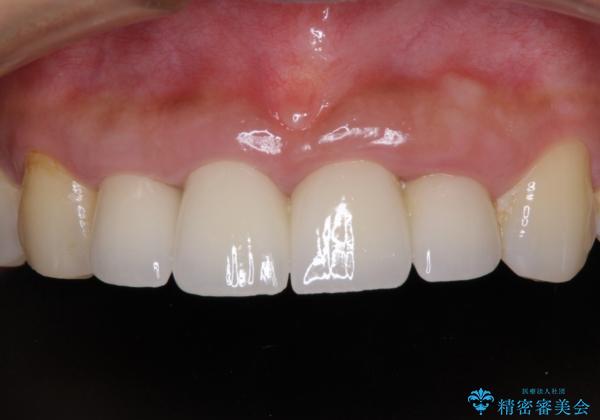

汚れた仮歯が気になる 前歯のオールセラミッククラウン

不適な仮歯の影響で歯肉が腫れていたため、新しい仮歯に替えた後に歯肉の腫れが引くのを待ち、オールセラミッククラウンにて補綴することとしました。

仮歯を変えたことで歯肉の腫れは引き、根管治療も功を奏して膿の出口はきれいに消退しました。